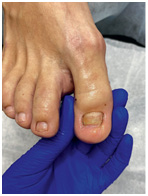

Результат работы за 5 месяцев: подолог использовал крючковые коррекционные системы, а хирург сделал пластику внутреннего бокового валика (из-за хронических воспалений боковой валик стал гипертрофированным и давил на ноготь, от чего клиент испытывал постоянный дискомфорт)